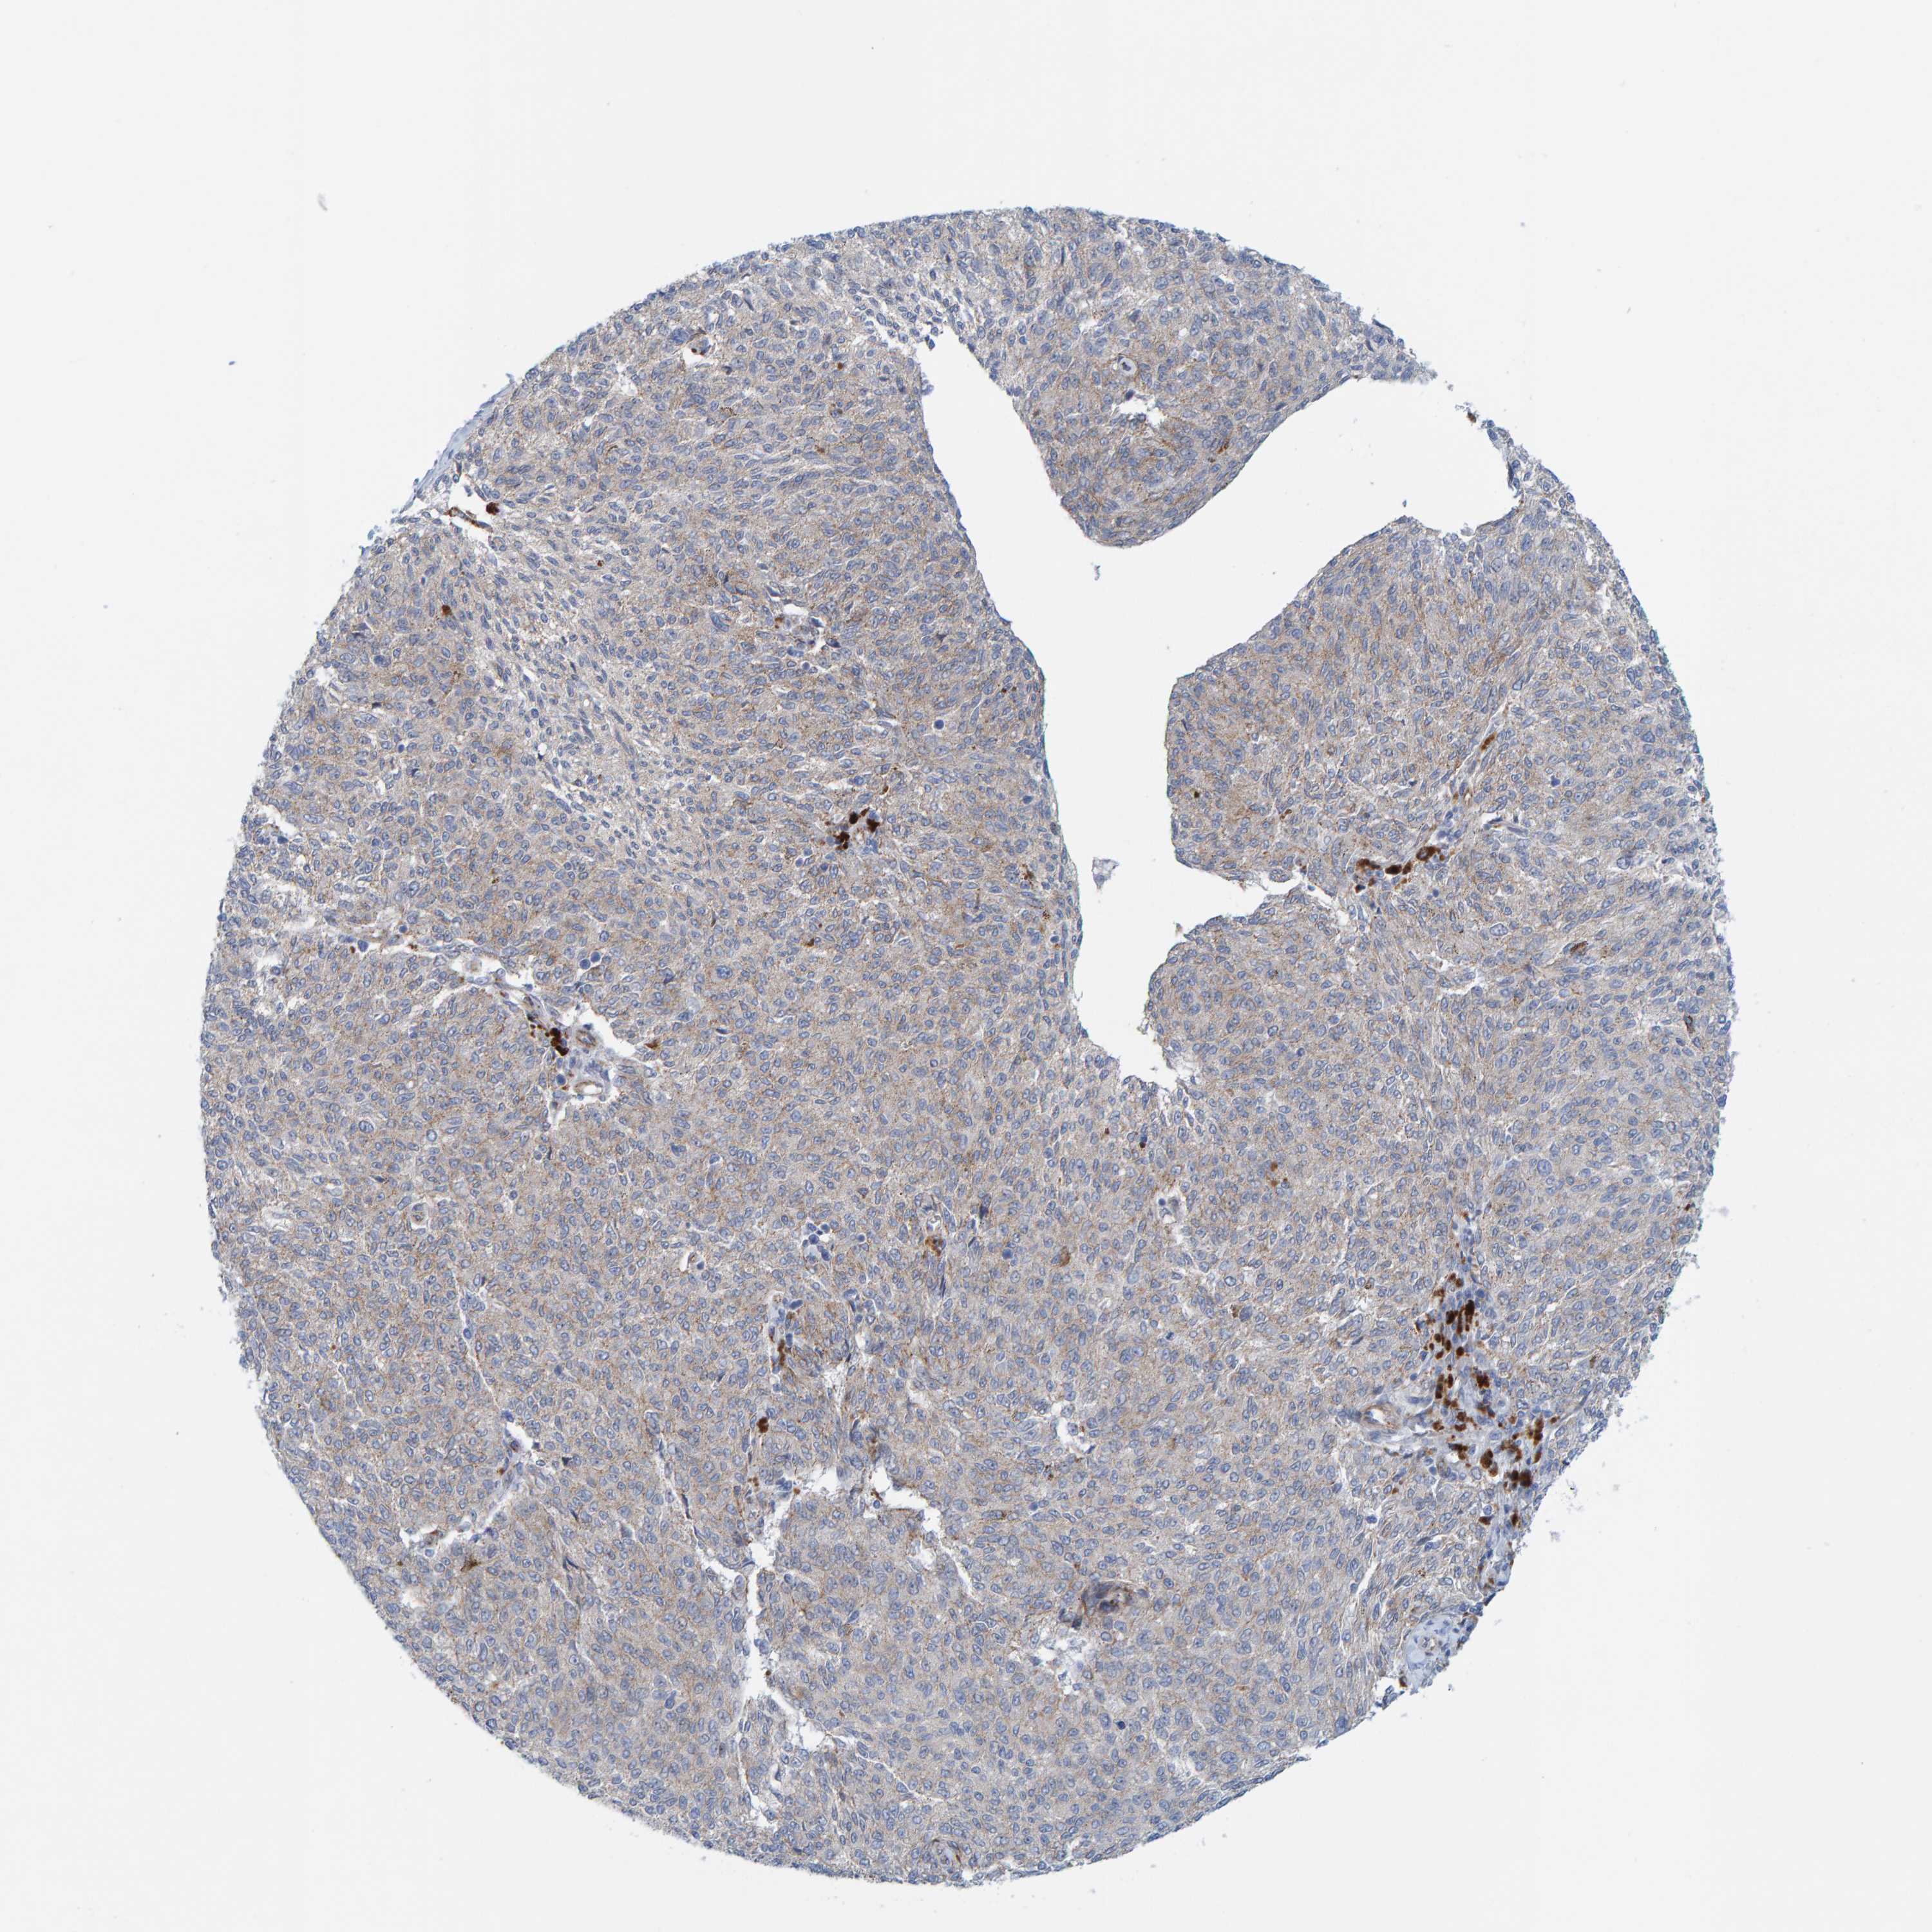

MELANOMA - Protein expressioni

A mouse-over function shows sample information and annotation data. Click on an image to view it in a full screen mode. Samples can be filtered based on level of antibody staining by selecting one or several of the following categories: high, medium, low and not detected. The assay and annotation is described here.

Note that samples used for immunohistochemistry by the Human Protein Atlas do not correspond to samples in the TCGA dataset.

Antibody stainingi

Antibody staining in the annotated cell types in the current human tissue is reported as not detected, low, medium, or high, based on conventional immunohistochemistry profiling in selected tissues. This score is based on the combination of the staining intensity and fraction of stained cells.

Each image is clickable and will lead to virtual microscopy that enables deeper exploration of all samples and also displays staining intensity scores, fraction scores and subcellular localization as well as patient and tissue information for each sample.

Antibody HPA022849

Staining

High

Medium

Low

Not detected

Intensity

Strong

Moderate

Weak

Negative

Quantity

>75%

75%-25%

<25%

None

Location

Nuclear

Cytoplasmic/membranous

Cytoplasmic/membranous,nuclear

Malignant melanoma, NOS

Malignant melanoma, Metastatic site